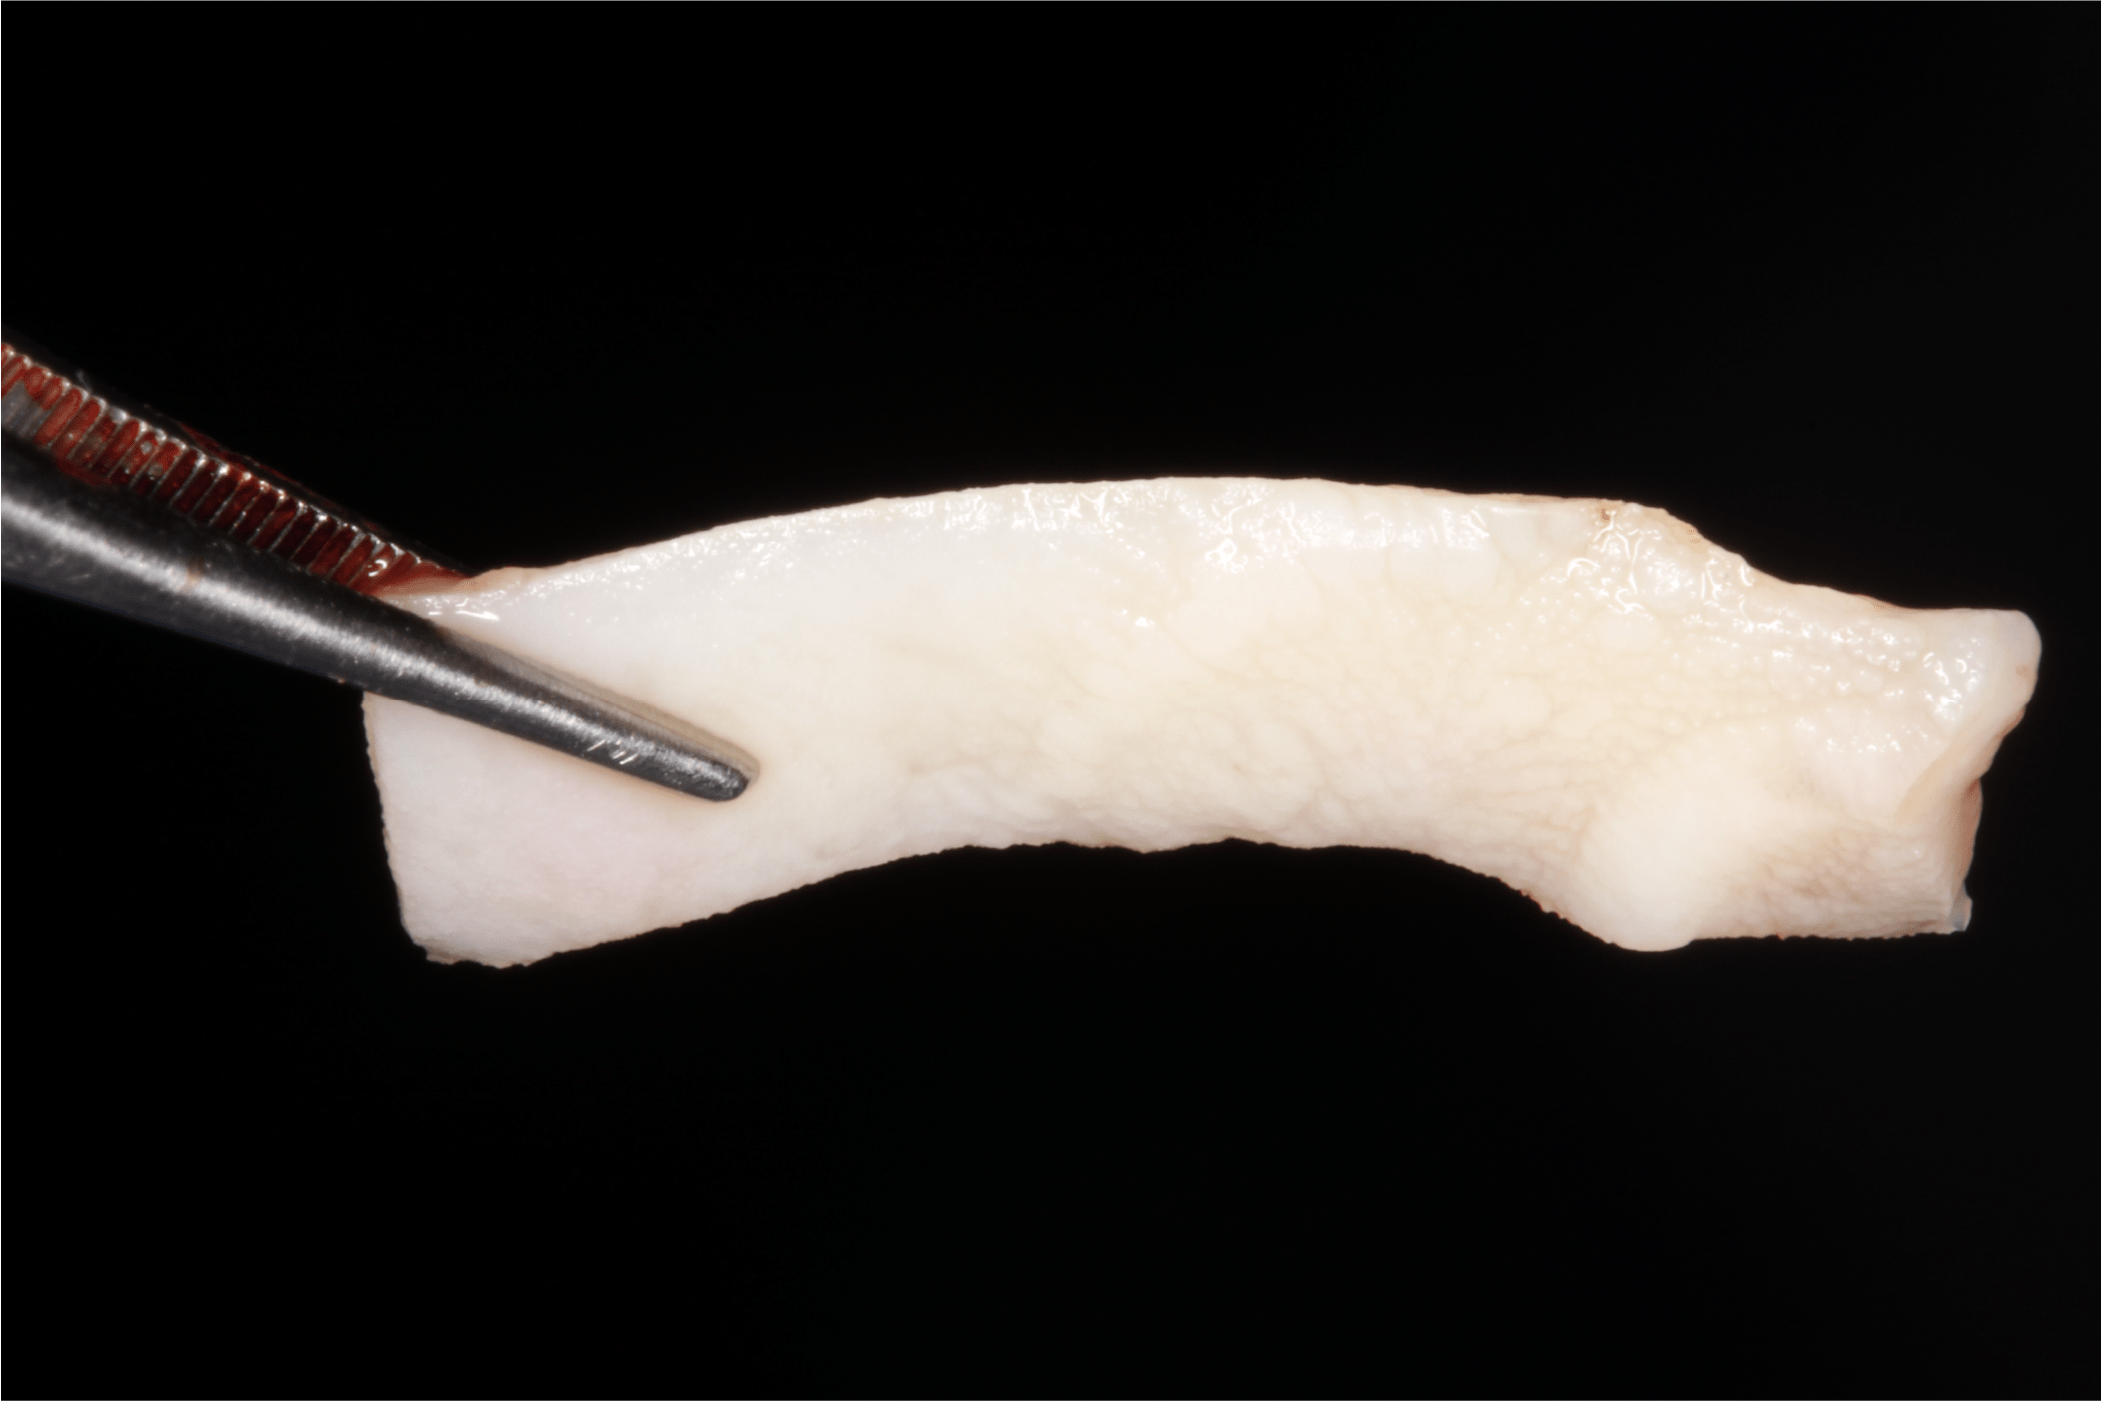

Posteriormente se realizan mediciones y se toma el IGL del paladar (Fig. 8).

Fig. 8